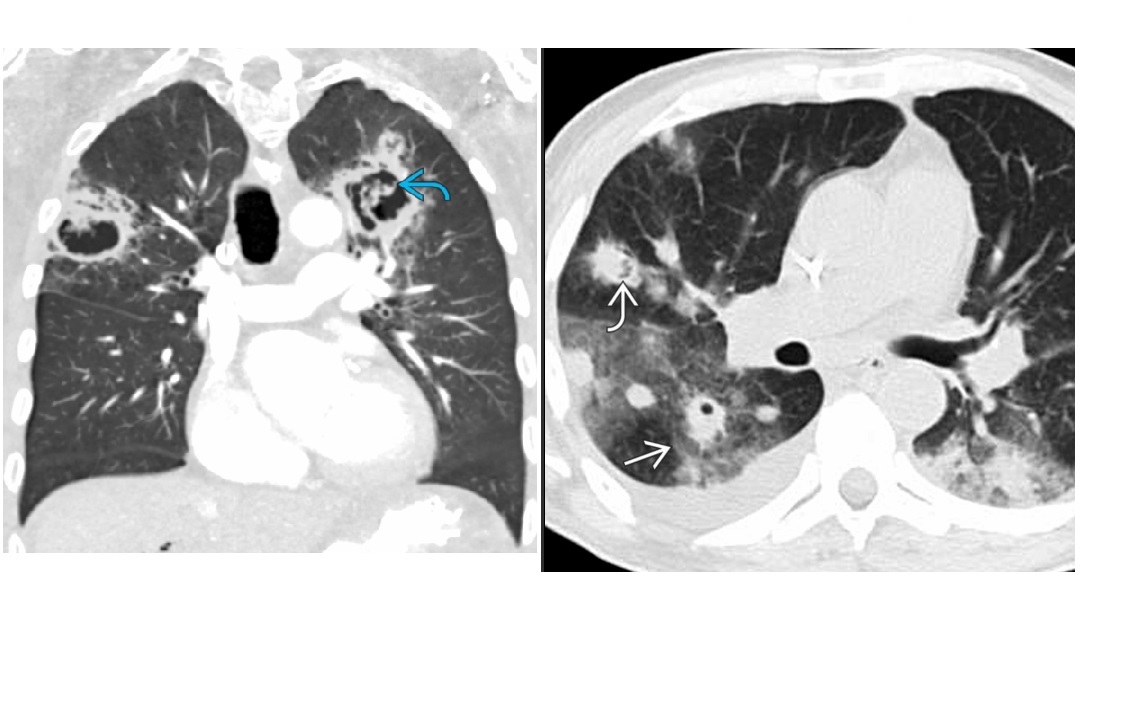

Septic emboli

Peripheral wedges shaped densities +/- cavity

Lower lobe predominant